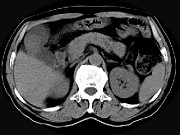

- 单项选择题男,45岁, 右季肋区疼痛,Murphy征阳性, B超提示胆囊息肉,CT所见如图, 最可能的诊断为 ( )